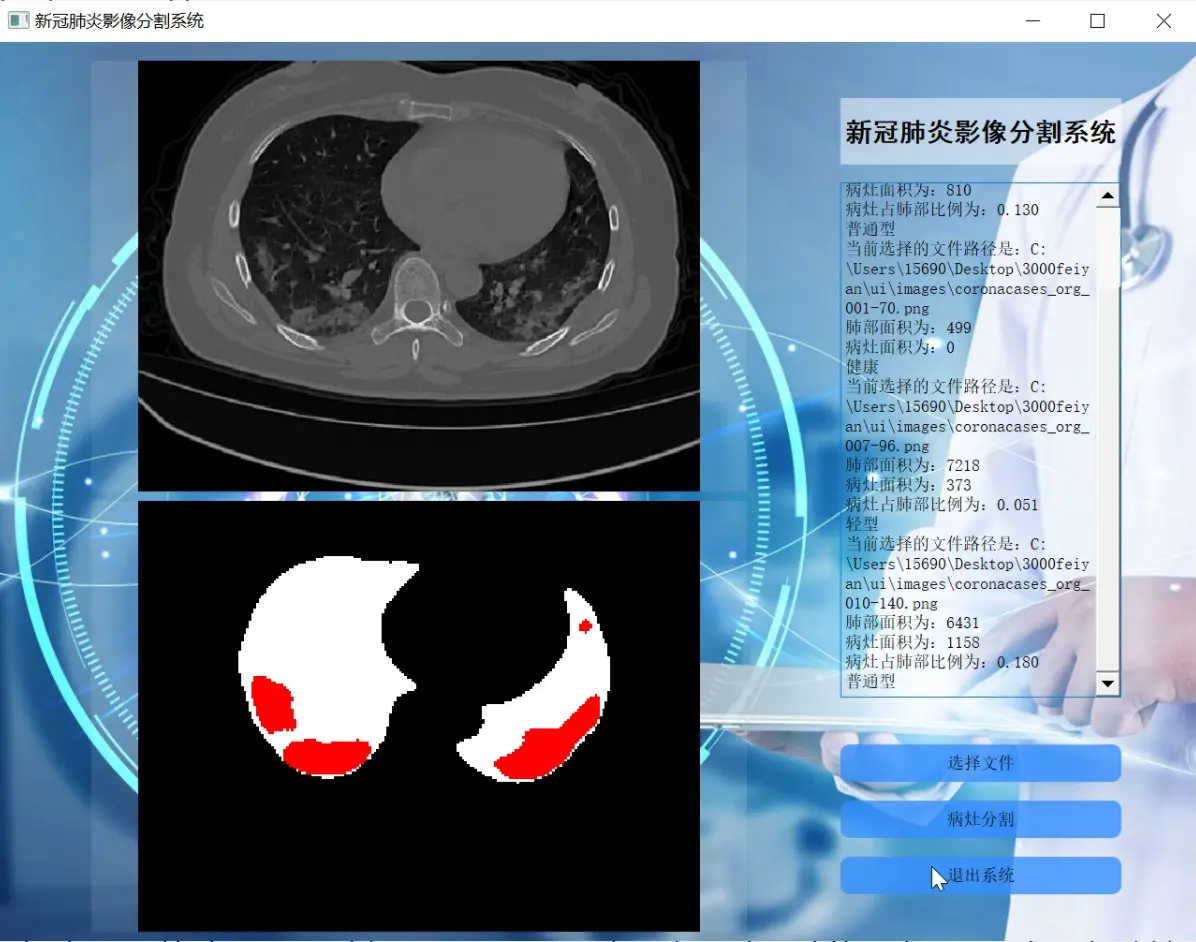

2.图片演示

这是一个使用PyQt5库创建的用户界面程序。该程序包含一个主窗口,窗口中有一个标签、三个标签框和两个按钮。标签用于显示图像,标签框用于显示文本信息,按钮用于触发相应的操作。

程序的主要功能是加载图像数据集并进行预测。它使用TensorFlow库加载图像数据集,并使用预训练的模型对图像进行分割。分割结果会显示在第三个标签框中。然后,程序会对分割结果进行后处理,计算病灶的面积,并根据面积比例判断病灶的严重程度。最后,程序会将结果显示在文本框中。

程序还包含一个线程类Thread_1,用于在后台运行分割和后处理的操作。当用户点击第一个按钮时,程序会创建一个Thread_1的实例,并将图像数据集的路径作为参数传递给它。然后,线程会在后台运行分割和后处理的操作,并将结果显示在界面上。

总之,这个程序是一个基于PyQt5和TensorFlow的图像分割应用程序,可以加载图像数据集并进行预测,然后根据预测结果进行后处理和分析。

这是一个使用TensorFlow和PyQt5实现的图像分割程序。程序文件名为ui.py。程序主要包括以下几个部分:

程序的主要功能是进行图像分割:通过调用bingzao_seg函数和fei_seg函数实现对病灶和肺的分割,并将分割结果显示在界面上。

总体来说,这个程序是一个基于MA-Unet模型的图像分割应用,可以对病灶和肺进行分割,并提供了图像预处理、数据加载和显示等功能。

该工程是一个改进Unet的新冠肺炎CT影像病灶分割系统,包含了预测、训练和用户界面三个主要部分。predict.py文件用于加载训练好的模型并对输入图片进行预测。train.py文件用于训练语义分割模型。ui.py和ui - 副本.py文件是用户界面程序,使用PyQt5库创建了一个界面,可以加载图像数据集并进行预测和分割。